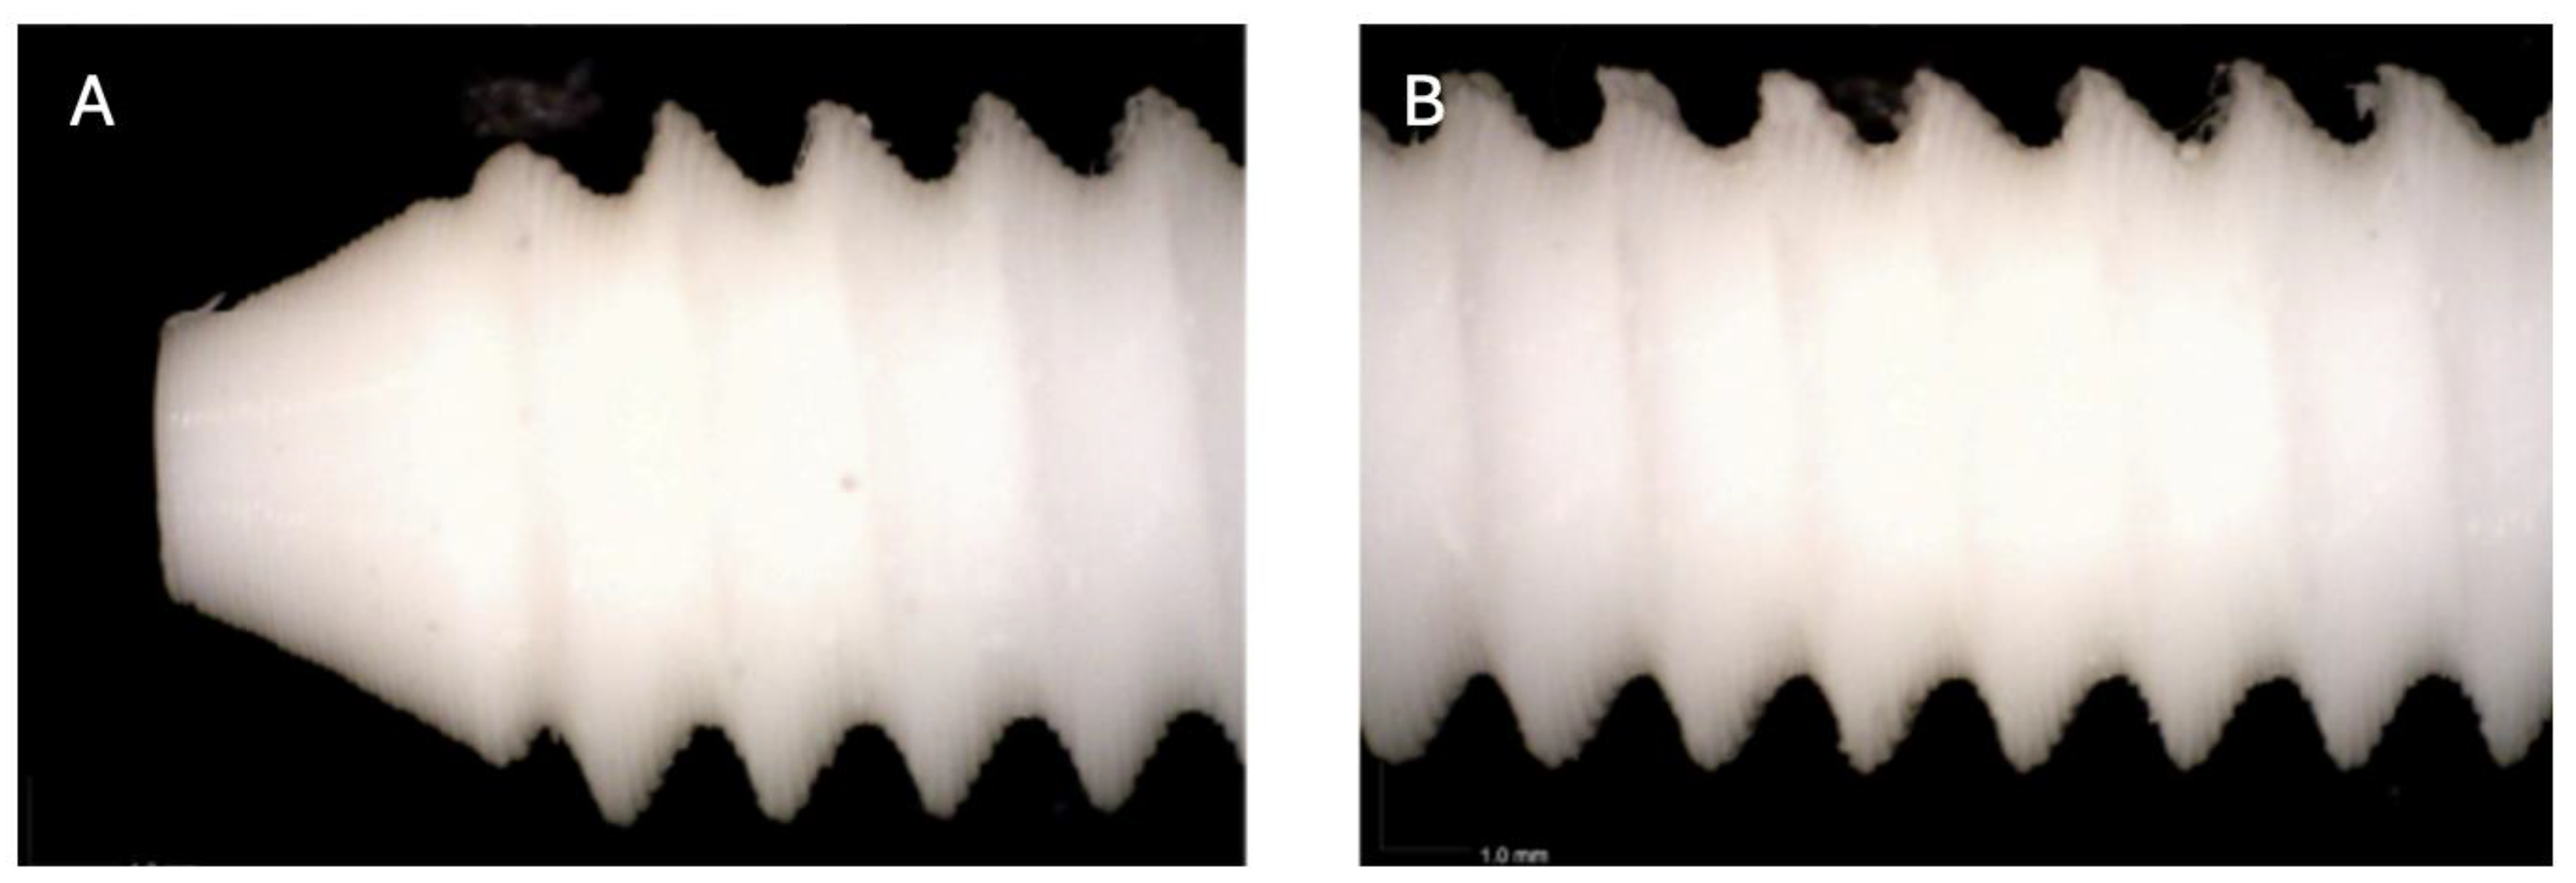

Figure 1. Photographic record of the PLA screw in its initial conditions prior to immersion. (A) top view showing the screw point and thread alignment; (B) side view highlighting the thread pitch and surface finish.

A photographic documentation of the PLA screws following the in vitro biodegradation testing is presented below. Visual comparison between the screws in their initial state (Figure 1, Figure 2, Figure 3, Figure 4, Figure 5, Figure 6, Figure 7, Figure 8, Figure 9 and Figure 10) and after 10 months of immersion in simulated body fluid (Figure 11) revealed evident morphological changes. Specifically, degradation was observed at the crests of the screw threads, where small PLA fragments were detected following prolonged exposure. These fragments were absent in the screws prior to immersion, indicating the initiation of a biodegradation process. Notably, the initial signs of this potential degradation mechanism were detectable from the fifth month of exposure onwards (Figure 6).